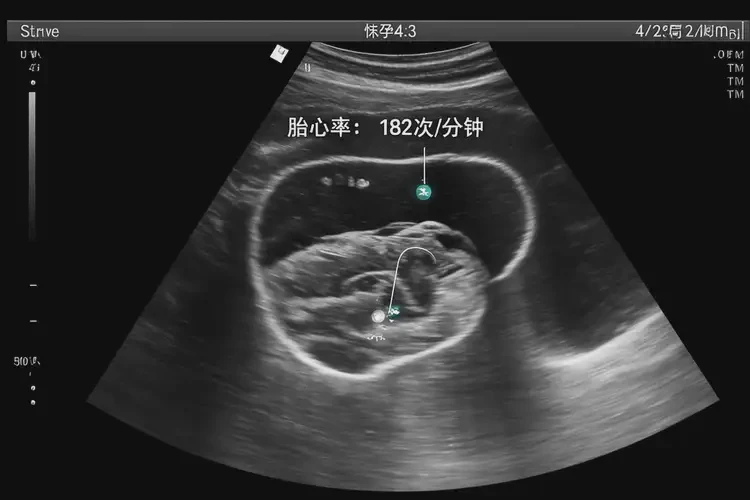

胎心率182次/分鐘

懷孕第2周胎心率達(dá)到182次/分鐘,這屬于正常范圍。胎心率是指胎兒心臟每分鐘跳動(dòng)的次數(shù),通常在120-160次/分鐘之間被認(rèn)為是正常的。在懷孕早期,胎心率可能會(huì)稍高一些,尤其是在胎兒活動(dòng)時(shí)。以下是關(guān)于胎心率的詳細(xì)解釋: